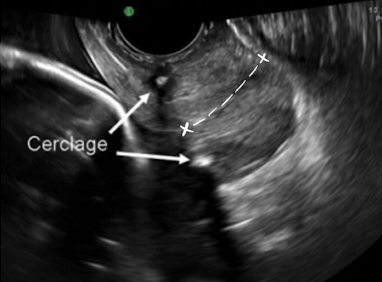

cervical cerclage

tx for cervical incompetence

cervix is stitched closed to prevent preterm birth

SONO: cervical cerclage

post-cerclage procedure; imaged transvaginally

cerclage stitches are echogenic with posterior shadowing

serial scans may be done to ensure cerclage remains secure and cervix is closed

what are the arrows pointing to?

cervical cerclage stitches